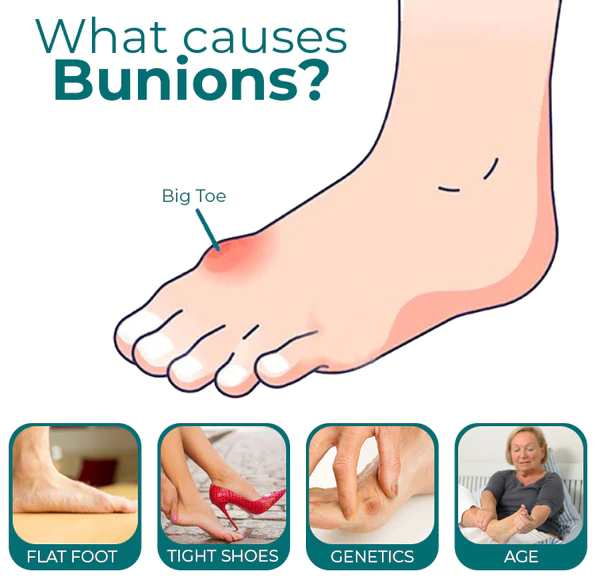

When you have bunions or overlapping toes, long days on your feet can be quite painful. By entering and soothing the underlying tissue to lessen hurting and discomfort, the RASSMAM™ BunionOut Relief Patch can assist in providing that pain relief in a natural way.

- RASSMAM™ BunionOut Relief Patch are made to straighten your big toe and put it back in its proper place. It not only relieves your toe from the pain, swelling, and pressure brought on by bunions, but it also aids in reducing the bunion so that the joint won’t become misaligned once again. Relieve pain and overlapping toes without surgery.